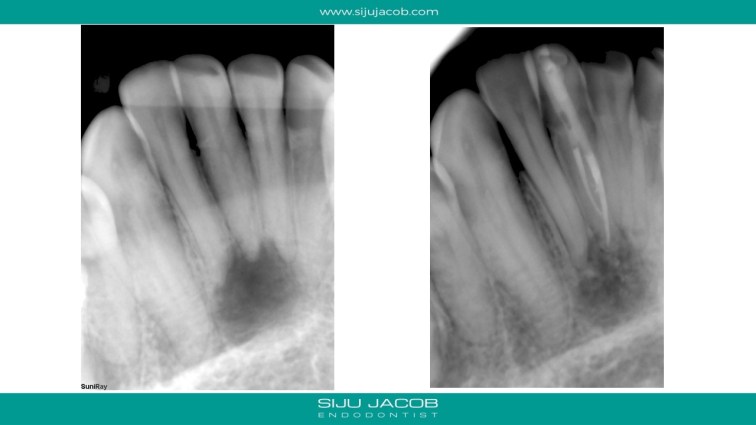

This patient had a lesion involving three teeth in the mandibular anterior region. He was seen by multiple clinicians and all of them had advised endo on 3 teeth followed by surgery. I treated just the one tooth which tested non-vital. I placed Long-term calcium hydroxide (6 months) to see some evidence of healing before obturation.